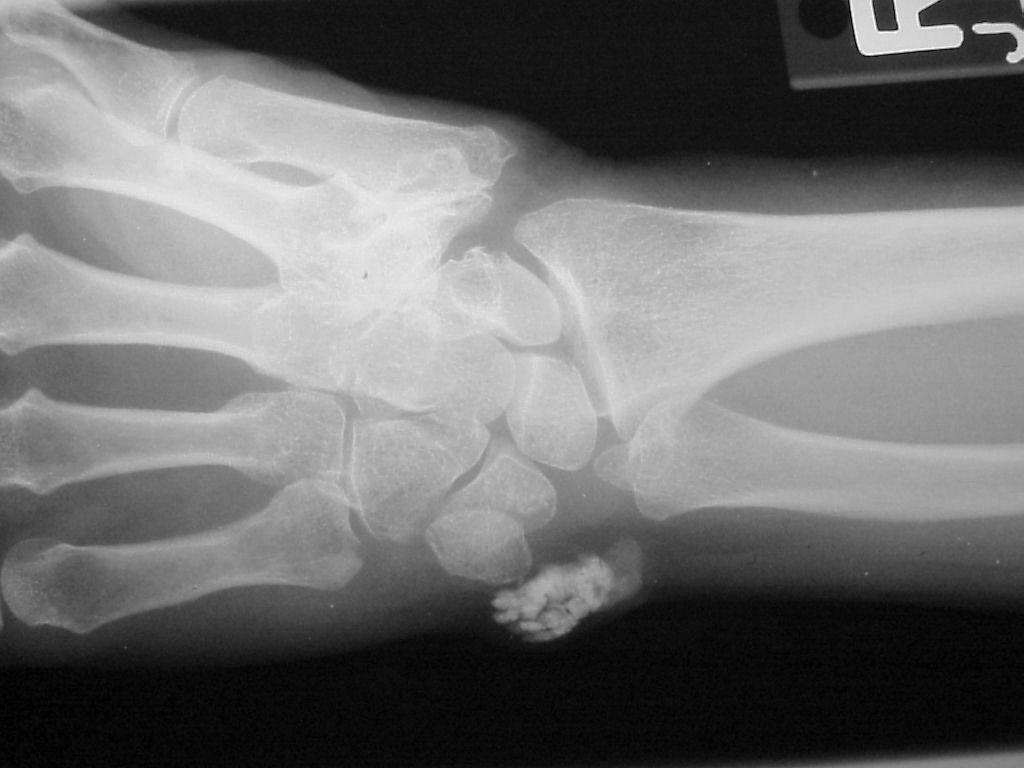

Isolated involvement around the flexor carpi ulnaris at the level of the wrist.